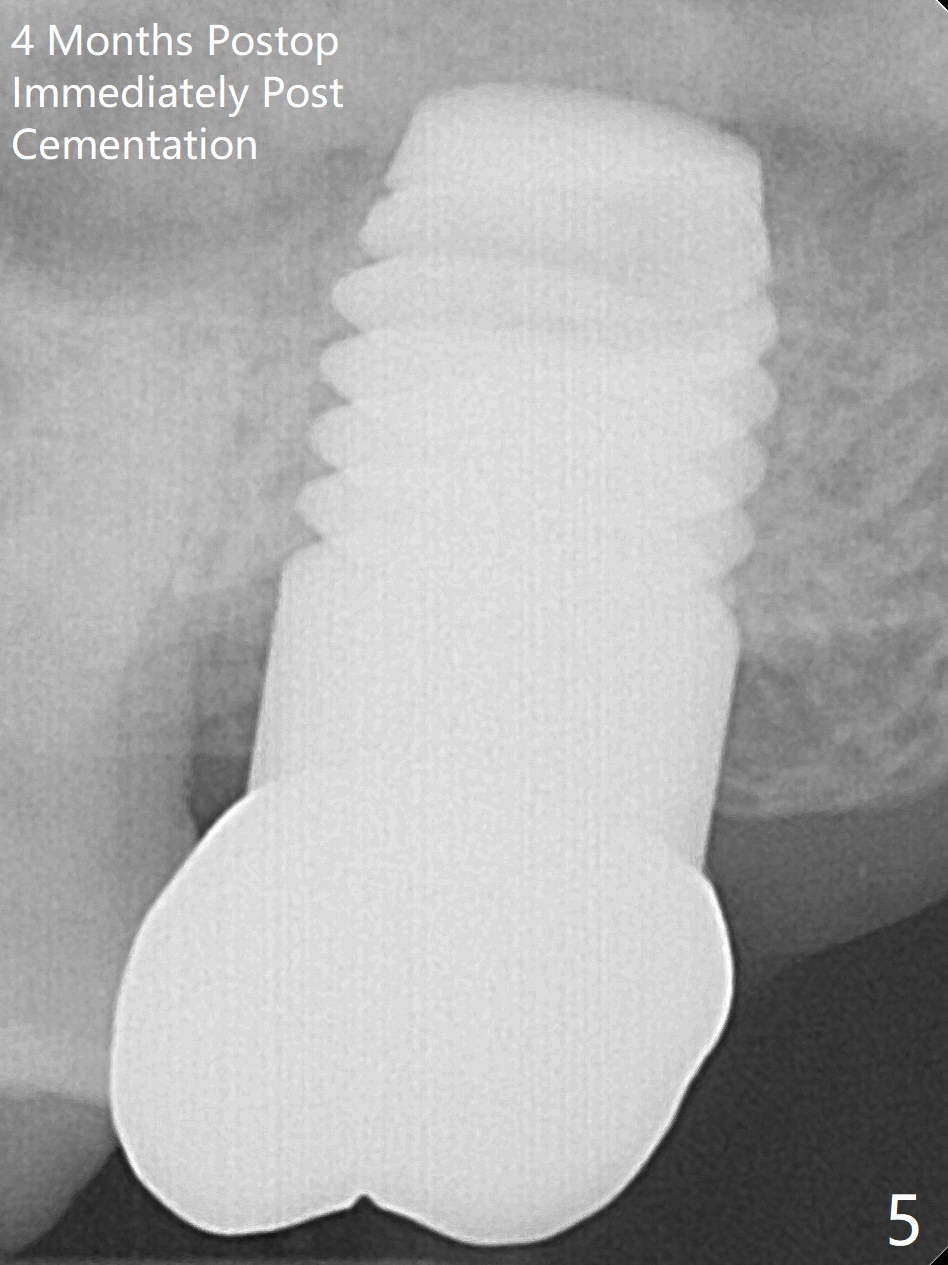

Initially the patient is reluctant to have the crack tooth extracted (Fig.1). Blood drawing for PRF fails. After extraction, the septum is confirmed to be short and thin. The bone density is moderate. When a 3.5 mm drill is being used, the osteotomy perforates into the mesiobuccal socket. A 5x10 mm IS implant achieves minimal stability. As 5.5, 6.0 and 7.0 mm cortical taps are inserted, primary stability is not obtained, as more bone is being removed at the level of the septum. When a 7x17 mm Tatum tapered tap is placed, it looks too small for the socket, as confirmed by measurement of a preop PA (Fig.2). Chronic infection associated with crack syndrome for 2 years may cause bone loss of the socket walls. Since the primary stability of a 8x17 mm tapered tap is not high (Fig.3), a 8x14 mm cylindrical implant is placed (after try in of its dummy one) with > 50 Ncm (Fig.4). The implant engages into the mesial and distal socket walls for stability. A 6x3 mm abutment is placed for an immediate provisional. In spite of difficult manipulation, the sinus membrane remains intact. Vanilla graft is placed for sinus lift and buccal and palatal gaps. Since IS implants are more or less cylindrical and if a 5 mm one does not achieve primary stability, a larger Tatum tapered tap should be tried immediately without using IS cylindrical taps. The patient returns 3 months postop, requesting early restoration before a trip to home country. The provisional has occlusal perforation. Final restoration is cemented nearly 4 months postop (Fig.5,6). The large implant makes the early restoration possible. However there is bleeding on probing palatal 1.5 years post cementation (Fig.7), suggesting palatal thread exposure. Return to Upper Molar Immediate Implant, Prevent Molar Periimplantitis (Protocols, Table), Armaments 6 Xin Wei, DDS, PhD, MS 1st edition 05/07/2018, last revision 05/08/2021